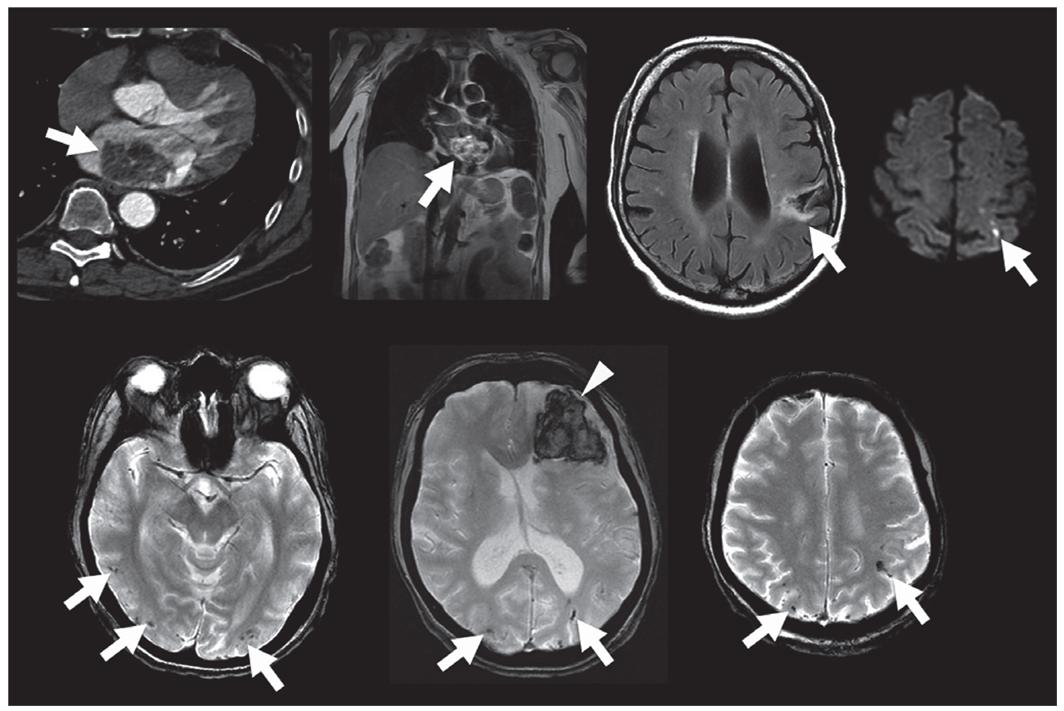

心脏粘液瘤 轴位胸部CT(a)、冠状位胸部MRI(b)示心脏粘液瘤;FLAIR示脑软化灶(c);DWI示急性点状梗死(d);T2*WI示ICH(f)和多发CMBs(e-g)。